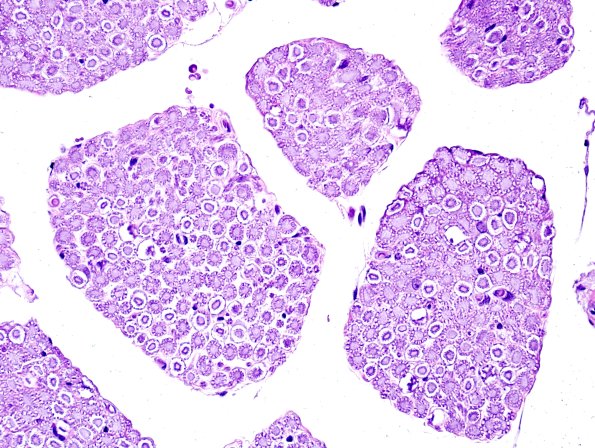

Washington University Experience | PERIPHERAL NEUROPATHY | 0 PNS ARTIFACTS | 5E Neurokeratin artifact (Monkey) H&E 1

This pattern is designated as a “wagon wheel” appearance in cross sections in monkey (5E) and Cheetah (5F); it is thought to represent autolysis. (H&E )